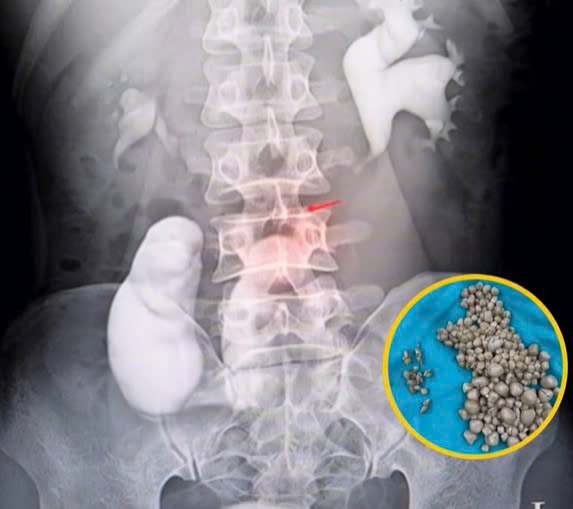

When Xiao Yu first arrived at the hospital, doctors suspected a standard infection. However, CT scans and ultrasounds revealed a kidney that was swollen with fluid and packed with stones of every size, ranging from fine grains to clusters nearly two centimeters wide. Most kidney stone patients have one or two stones, sometimes a handful. Seeing hundreds inside a single kidney was almost unheard of. Over time, these stones had blocked her kidney’s ability to filter waste properly, triggering infection and fever. Her body had reached a breaking point after years of silent damage.

Faced with a kidney packed with stones, doctors had no choice but to operate. They performed a procedure known as percutaneous nephrolithotomy, which involves removing stones through a small incision in the back. Over several hours, surgeons extracted hundreds of stones, filling multiple trays. The sheer volume shocked the medical team and quickly drew public attention. Fortunately, the surgery was successful. Xiao Yu’s pain subsided, her fever resolved, and she was discharged after several days of recovery.